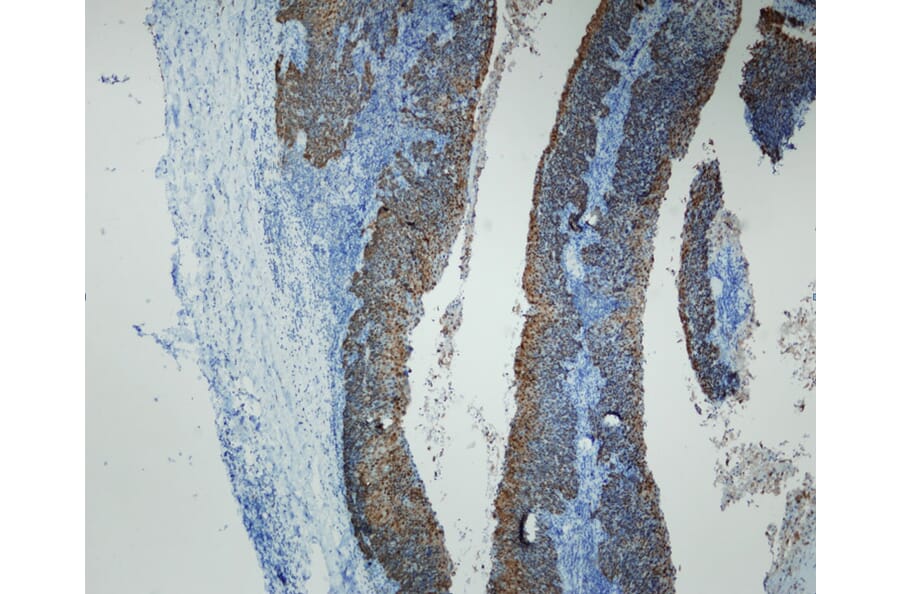

High grade squamous intraepithelial lesion of the uterine cervix (in contrast with non-dysplastic metaplastic squamous epithelium). Shows strong and specific positive immunostaining of dysplastic and neoplastic epithelium, with no reactivity in normal epithelial and stromal structures. Formalin fixed, paraffin embedded human tissues (4µm sections) stained with Anti-p16 Antibody (A8237).